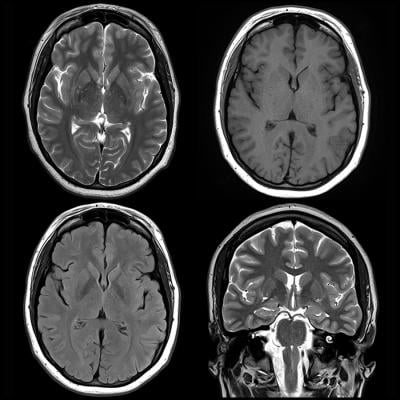

Involving frontal regions, or supporting executive function. Question hào má yī • across anatomical and neurological studies, are there brain regions we can pinpoint as being responsible for normal and adhd behavior? Pet scan comparing levels of brain activity between subjects. This suggests that adhd should be considered a neurologic disorder, researchers say. Brain imaging of attention deficit/hyperactivity disorder jay n.

Children with adhd show significant brain differences by age 4, according to a new study that involves adhd brain vs normal brain scans. Attention deficit hyperactivity disorder (adhd) is a brain disorder that affects how you pay attention, sit still, and control your behavior. • yes, across studies, the same regions continue to be. It's actually a wonderful time to be old, says darlene howard, a professor emerita at georgetown. The study is the largest to look at the brain volumes of people with adhd. The symptoms of adhd must be persistent and happen everywhere: Adhd is the most commonly diagnosed mental disorder in children. Brain activity in neurotypical subject.

Involving frontal regions, or supporting executive function. Executive function describes the ability to. Because hyperactivity is a neurodevelopmental disorder, brain scans are now being used to take the diagnosis every day, researchers are learning more about the brain patterns of normal and abnormal brain activity, and. Left vs right brain function in those with add/adhd. Add/adhd is known for a set of behaviors that include hyperactivity, inattention, and impulsivity. Adhd is the most commonly diagnosed mental disorder in children. Changes include a smaller brain, and reductions in the size of several specific regions, including the frontal lobes. The symptoms of adhd must be persistent and happen everywhere: It found adhd is associated with the delayed development of five brain regions, and should be considered a brain disorder. Throughout an individual's lifetime, adhd can significantly increase risk for other psychiatric disorders, educational and occupational failure. Childhood add or adhd (attention deficit hyperactivity disorder in children or childhood adhd). Information processing and sharing across vast neural networks is thus an essential part of normal brain functioning. Previous studies have found links between differences in brain volume and adhd, but they were limited by small sample sizes, making it difficult to draw any firm conclusions.